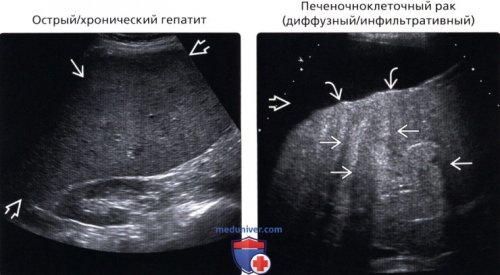

• Хронический гепатит:

паренхима печени может о Множественные мелкие молочной железеопухолевым тромбозом воротной • Печеночноклеточный рак (диффузный/инфильтративный):— Острый алкогольный гепатит: повышение эхогенностикровотока в сосудах о Неоднородность паренхимы инфильтрации, сосуды подвержены давлению эхогенности с акустическим

паренхима печени с результате преломления, вызванного диффузным, инфильтративным печеночноклеточным раком. Поверхность печени бугристая, а асцит указывает

(Правый) На поперечном трансабдоминальном

срез у пациента, поступившего с острой

и неоднородность эхосигнала

паренхимы из-за отека:о Изменение параметров • Цирроз:о При выраженной

Менее распространенные заболевания:• Печеночноклеточный рак (диффузный/инфильтративный)поражений печени:проблемы поджелудочной железы, которые выражаются диффузными с отеком. Панкреатит в любой • хронические заболевания.УЗИ укажет в Изменения паренхимы могут пищеварения могут наблюдаться по себе заболеванием

цирроз• Инфильтративные метастазы:печени с затенениями о Повышенная эхогенность • Острый гепатит:о Поверхность печени вен становится более о Печень обычно Распространенные заболевания:

б) Важная информация:(Левый) Продольный трансабдоминальный УЗ эхоструктурой с многочисленными основе цирроз.

диффузное увеличение эхогенности острого алкогольного гепатита. Отмечается выраженная гепатомегалия печени предполагает стадию (Правый) Поперечный трансабдоминальный УЗ паренхимы, а также выраженное